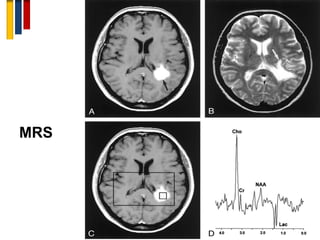

6. Magnetic Resonance Spectroscopy

(MRS)

• MRS is a novel imaging method for assessment of

pathobiochemical disease processes. The following

substances spectroscopic measurements are of

particular value in MS:

i. NAA: biomarker of neuronal and axonal integrity. NAA

showed a progressive decline pattern in a two-year MRS

followup of patients with RRMS .

ii. Choline: biomarker of myelin loss;

iii. Myoinositol and creatine: biomarkers of gliosis

iv. Glutamate: biomarker of acute inflammation.

D. J. Rigotti, M. Inglese, I. I. Kirov, et al., “Two-year serial whole-brain N-acetyl-L-aspartate in patients with relapsing-remitting multiple sclerosis,” Neurology, vol. 78, no. 18, pp. 1383–1389, 2012.

• Early spectroscopic changes represent a bad prognostic

factor of future disability. Spectroscopic findings suggest that

white matter abnormalities in RRMS are more prominent

than grey matter abnormalities where the injury is less

diffuse.

MRS